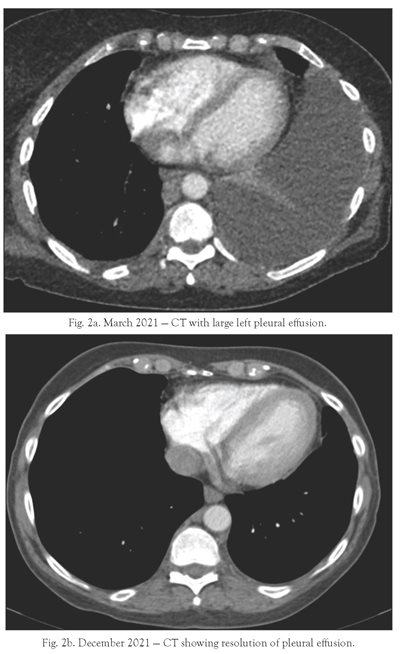

She then underwent a CT abdomen/pelvis on April 1, 2021, which revealed: “Bilateral retroperitoneal adenopathy consistent with the history of lymphoma. Subcutaneous soft tissue nodule likely representing a tumor deposit is also noted in the RIGHT buttock” (see Figs. 2a and 3-5). Prior to this CT scan, she had never had adenopathy noted on a CT scan.

After the CT scans, different options were discussed with the patient including watchful waiting; Rituxan®; more cycles of Treanda®/Rituxan®; and the addition of a new BTK agent, Brukinsa®. The patient chose watchful waiting, monitoring of her IgM levels and viscosity monthly, as well as undergoing a CT scan 12 weeks later to follow-up on her adenopathy. Other options would have been considered if she developed increasing pleural effusion, increasing adenopathy, or increasing creatinine levels, but these did not occur. She continued to have fluid drainage of her pleural catheter of about 300 ml/week until November 2021, at which time her fluid drainage ceased completely. Her catheter was removed in November 2021 by Interventional Radiology. CT scans in December 2021 revealed no further evidence of disease (see Figs. 2a, 2b, 3-5, and 9).